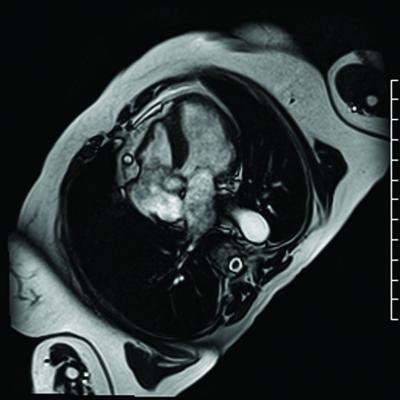

CMR is an MRI scan that focuses on the area around the heart. Unlike SPECT, CMR does not involve ionizing radiation and the large CE-MARC (Clinical Evaluation of Magnetic Resonance imaging in Coronary heart disease) study demonstrated that CMR had high diagnostic accuracy, with higher sensitivity and negative predictive value compared with SPECT.

However, data on the prognostic value of CMR remain limited. A predefined objective of CE-MARC was to assess the ability of CMR and SPECT to predict MACE at five-year follow-up. To do so, researchers studied 752 patients from the CE-MARC study who were being investigated for suspected coronary heart disease. The patients were scheduled to undergo CMR and SPECT in random order, followed by X-ray coronary angiography (the reference standard) within four weeks. The investigators followed up with patients every year for five years to assess for MACE.

The researchers found that at five-year follow-up, CMR was a stronger predictor of risk for MACE than SPECT, independent of clinical cardiovascular risk factors, angiography result or initial patient treatment. The researchers conclude that CMR should be considered a robust alternative to SPECT for the diagnosis and management of patients with suspected coronary heart disease.